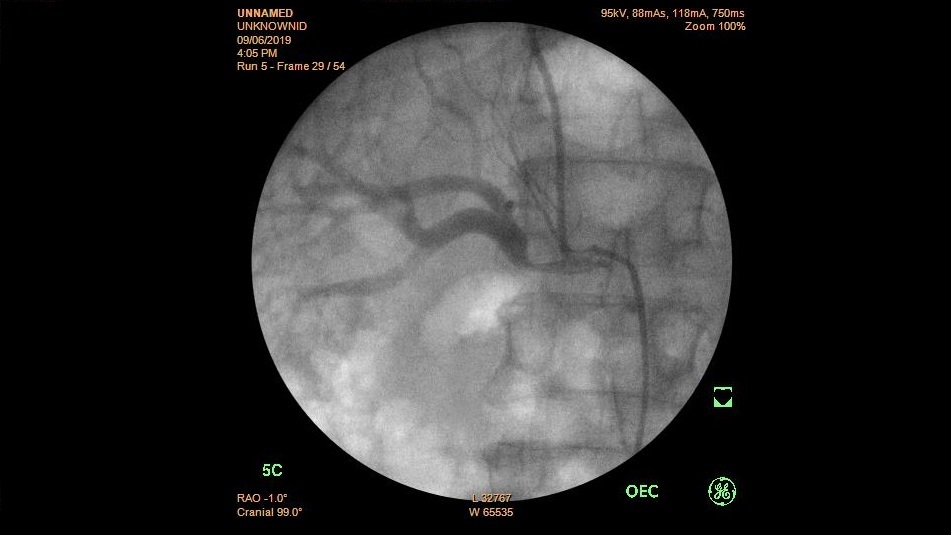

Dẫn lưu và đặt Stent đường mật qua da xuyên gan (PTBD) trong xử trí vàng da tắc mật tại Bệnh viện Trường Đại học Y Dược Huế

Vàng da tắc mật là một bệnh cảnh lâm sàng nặng và thường gặp. Shock nhiễm trùng đường mật là một trong những biến chứng nguy hiểm của tắc mật với tỷ...